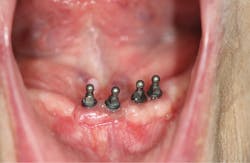

It was decided that mini-implants would be placed, and following a period of healing, the lower denture would be relined using a soft silicone material that would increase retention and provide a comfortable base against the tissues (figure 1). Four 2 mm by 10 mm Lew MDI collared o-ball endosseous titanium screw implants (Park Dental Research Corp.) were surgically placed. For cases in which a patient’s manual dexterity is limited, typical retention between the o-balls and metal housing attachments may be too heavy for the patient to manipulate. The treatment opted for was a soft reline that would provide milder retention, while completely covering the implants.

Figure 1: Mini-implants in the patient’s mouth